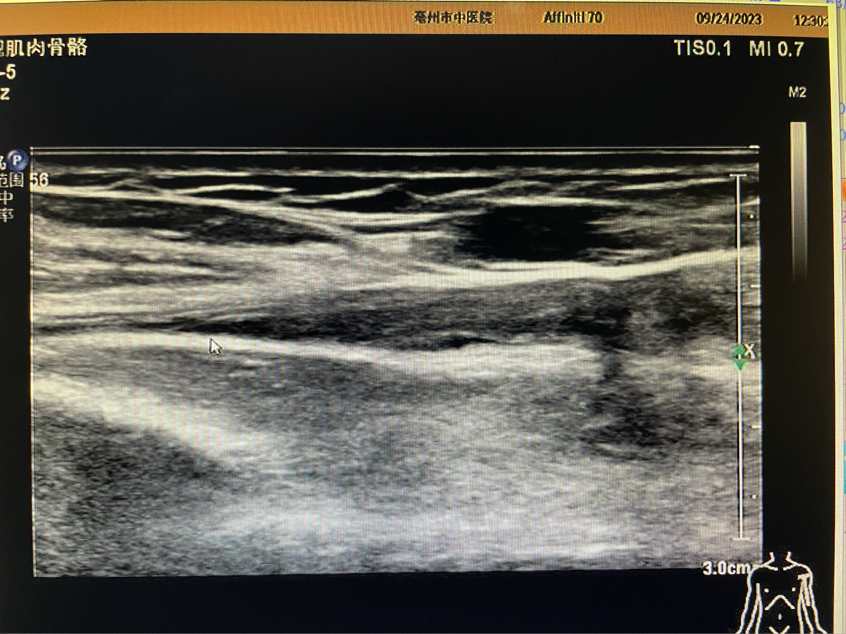

左側肱二頭肌長頭肌腱遠端斷端位置(箭頭)

肌骨超聲檢查是我院超聲科新開展的檢查項目。超聲科劉剛醫(yī)生為患者進行詳細肌骨超聲檢查,檢查所見:左側肱骨頭大小結節(jié)間溝空虛,代之以液性暗區(qū),較厚處約1.5mm,肱二頭肌長頭肌腱連續(xù)性中斷,斷端遠端攣縮,周圍可見厚約3.6mm液性暗區(qū)。檢查意見:左側肱二頭肌長頭肌腱完全斷裂伴周圍積液。